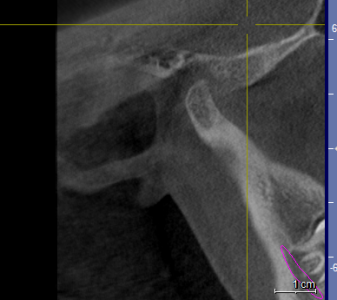

Здравствуйте! У моей дочери 16ти лет проблема с ВНЧС. При ношении брекетов ей вытягивали нижнюю челюсть, выравнивали прикус и зубы , в частности - клыки выпирающие выравнивали. А через 1,5 года после снятия в одно прекрасное утро не смогла открыть рот. Нам советовали делать лазер, становилось легче. Так было 2 раза. А теперь по утрам, если спит на правой щеке, то челюсть правую заклинивает. Голова сильно болит в висках. Связано ли это с брекетами или другая причина может быть? Читая в интернете об этой проблеме, поняла, что это дело очень тонкое и непростое, испортить жизнь ребенку можно запросто. А еще советуют мануального терапевта. Куда пойти ? У нас есть КТ в 3Д и еще нас на МРТ направили. Может ли мануальный терапевт решить эти проблемы? Знакомый стоматолог сказал, что если челюсть поправят, то прикус может нарушится. А мануальный говорит - приходите - все исправим, даже снимков ему не надо. .Теперь хочу выяснить у специалистов, как все таки поступить. К кому пойти сначала. Очень Вам буду благодарна за совет. Вот еще сделала скриншоты томографии